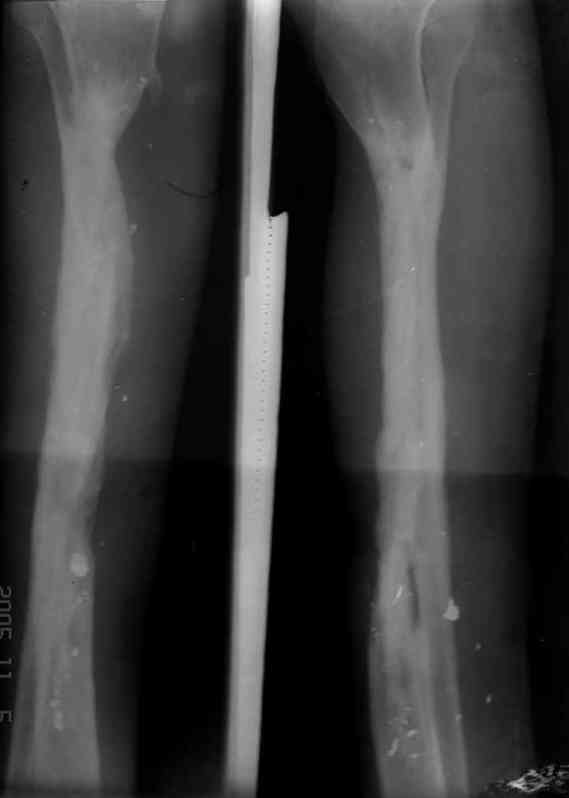

Пациент 19 лет, производственная травма, придавлен тяжелой плитой. Политравма (ISS 21).

1 - рентгенограмма (прошу прощения за качество) при поступлении;

2 - внешний вид голени;

Произведено ПХО, acute shortening (5 см), фиксация стержневым аппаратом Hoffman.

3,4 - через 4 недели наложен спице-стержневой аппарат, произведена остеотомия большеберцовой кости в верхней трети, раны зажили, проводилась дистракция в аппарате.

5, 6 - через 2,5 мес после травмы выполнен закрытый остеосинтез блокируемым штифтом.